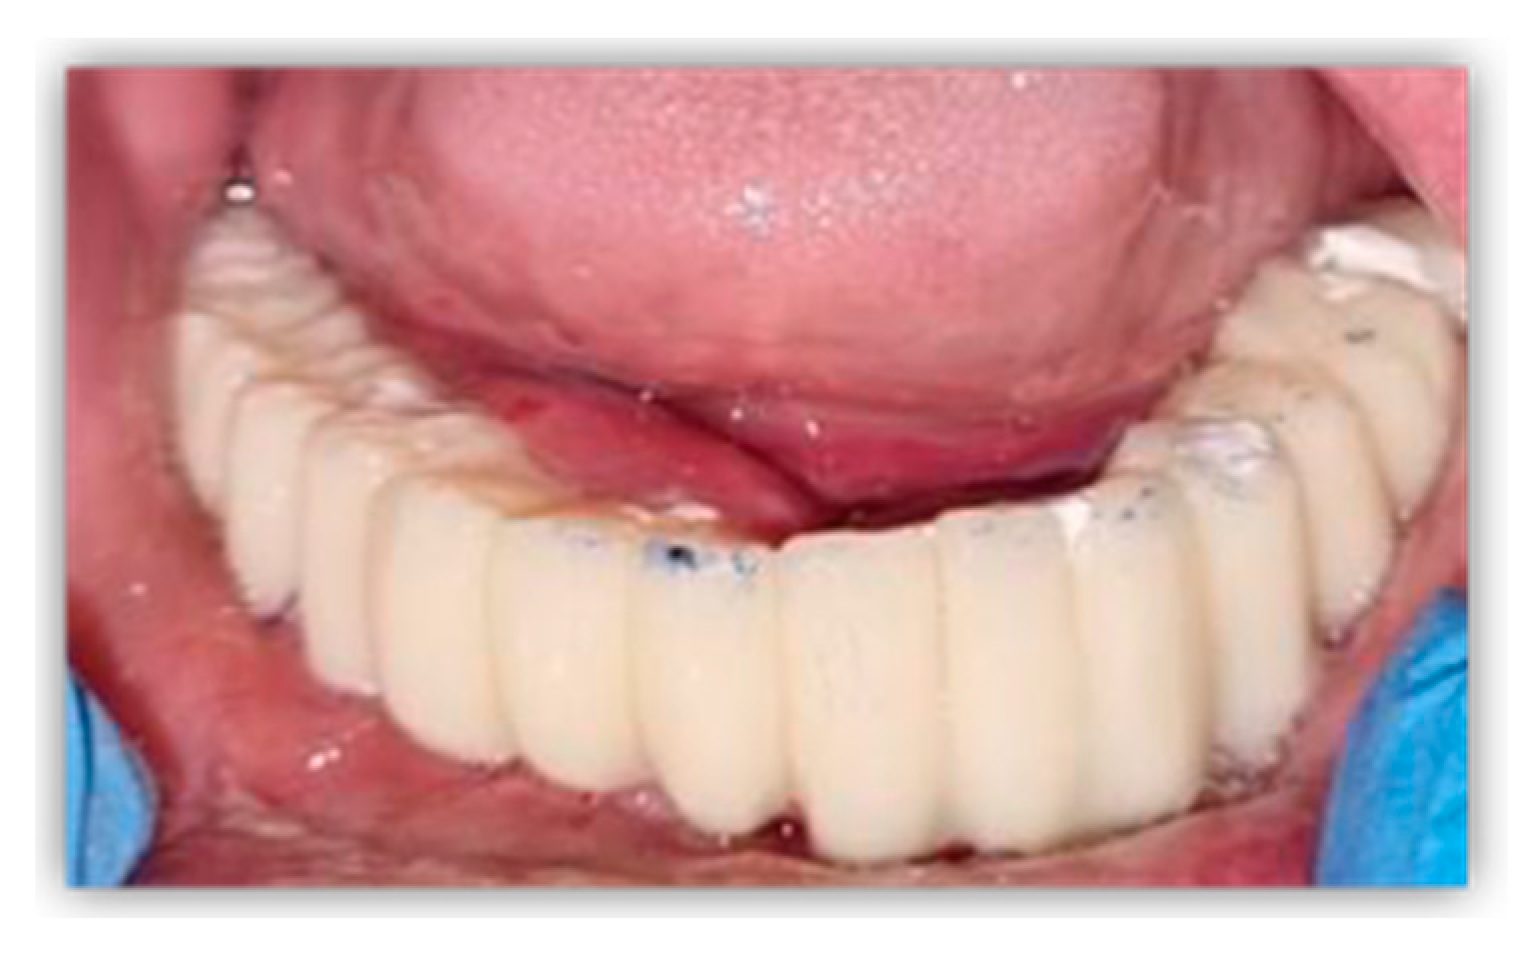

2. Case Report